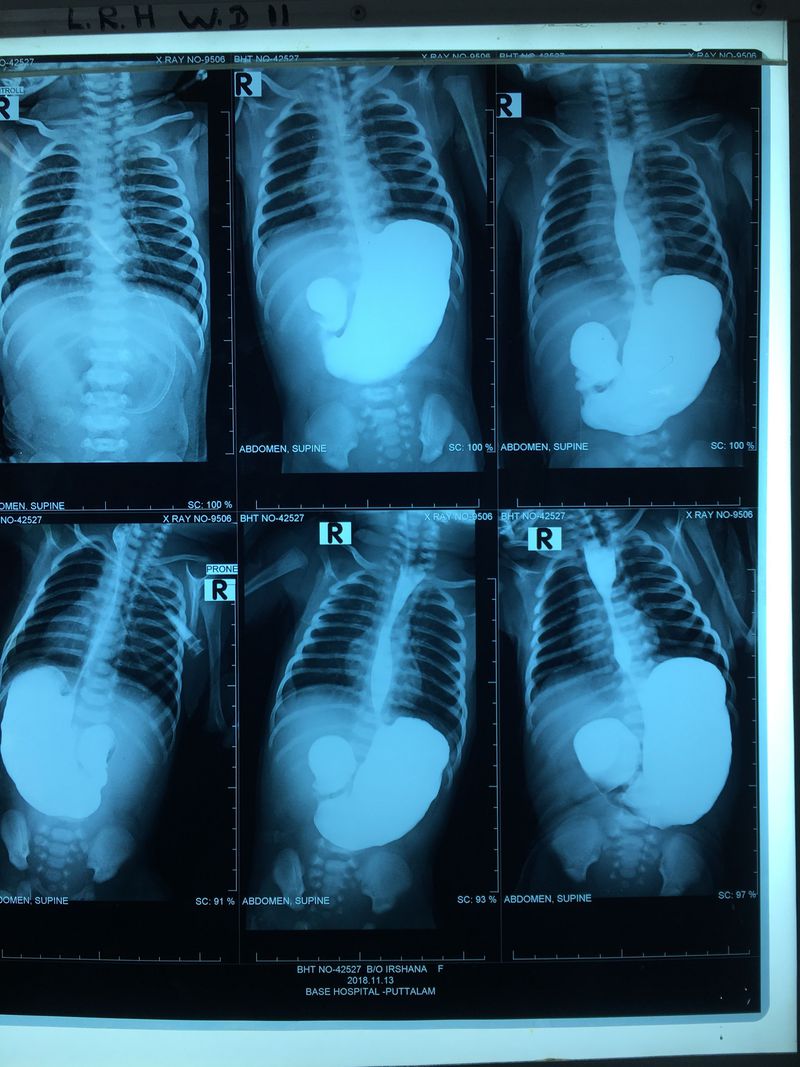

DOUBLE BUBLE SIGN

This 3 months year old baby presented with severe vomiting and failure to thrive. Initial investigations revealed congenital duodenal atresia! Exclusion of Choledochal cyst was done by Ultrasound.